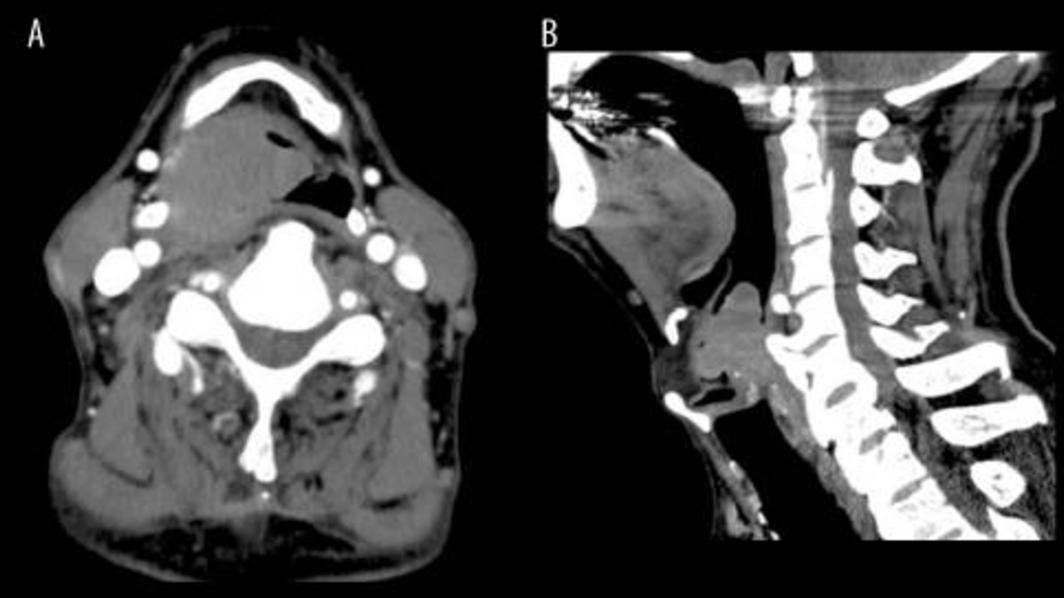

一名74岁老年患者因吞咽困难就诊,患者无疼痛。该患者没有相关病史。内镜检查显示右下咽肿瘤占据声门(图1)。肿瘤表面光滑,无出血迹象。计算机断层扫描显示下咽有一个40毫米的肿物(图2)。淋巴结无肿大。

图2 计算机断层扫描显示下咽有一个40毫米的肿块,压迫气道。(A) 轴向;(B) 矢状